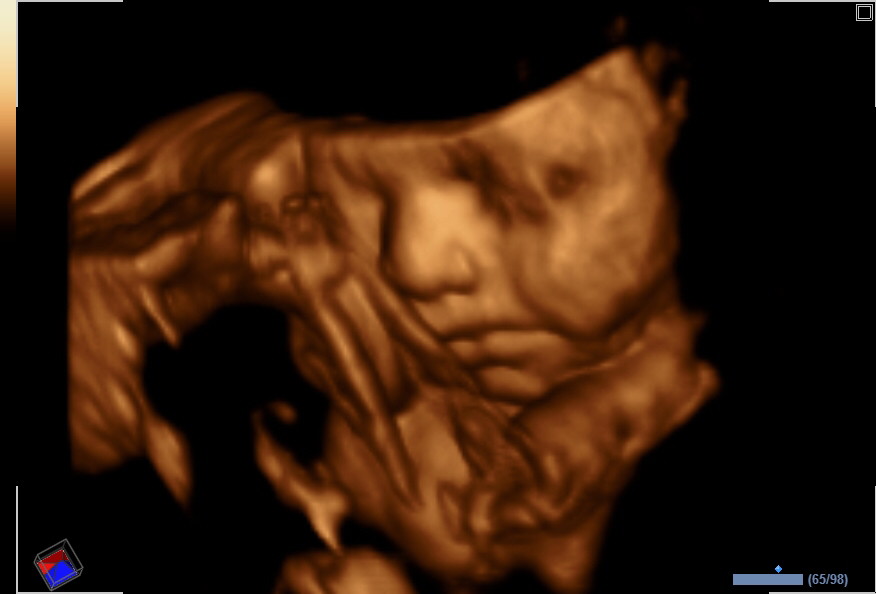

Bun, apakah kamu masih menyimpan video USG (Ultrasonografi) si kecil?